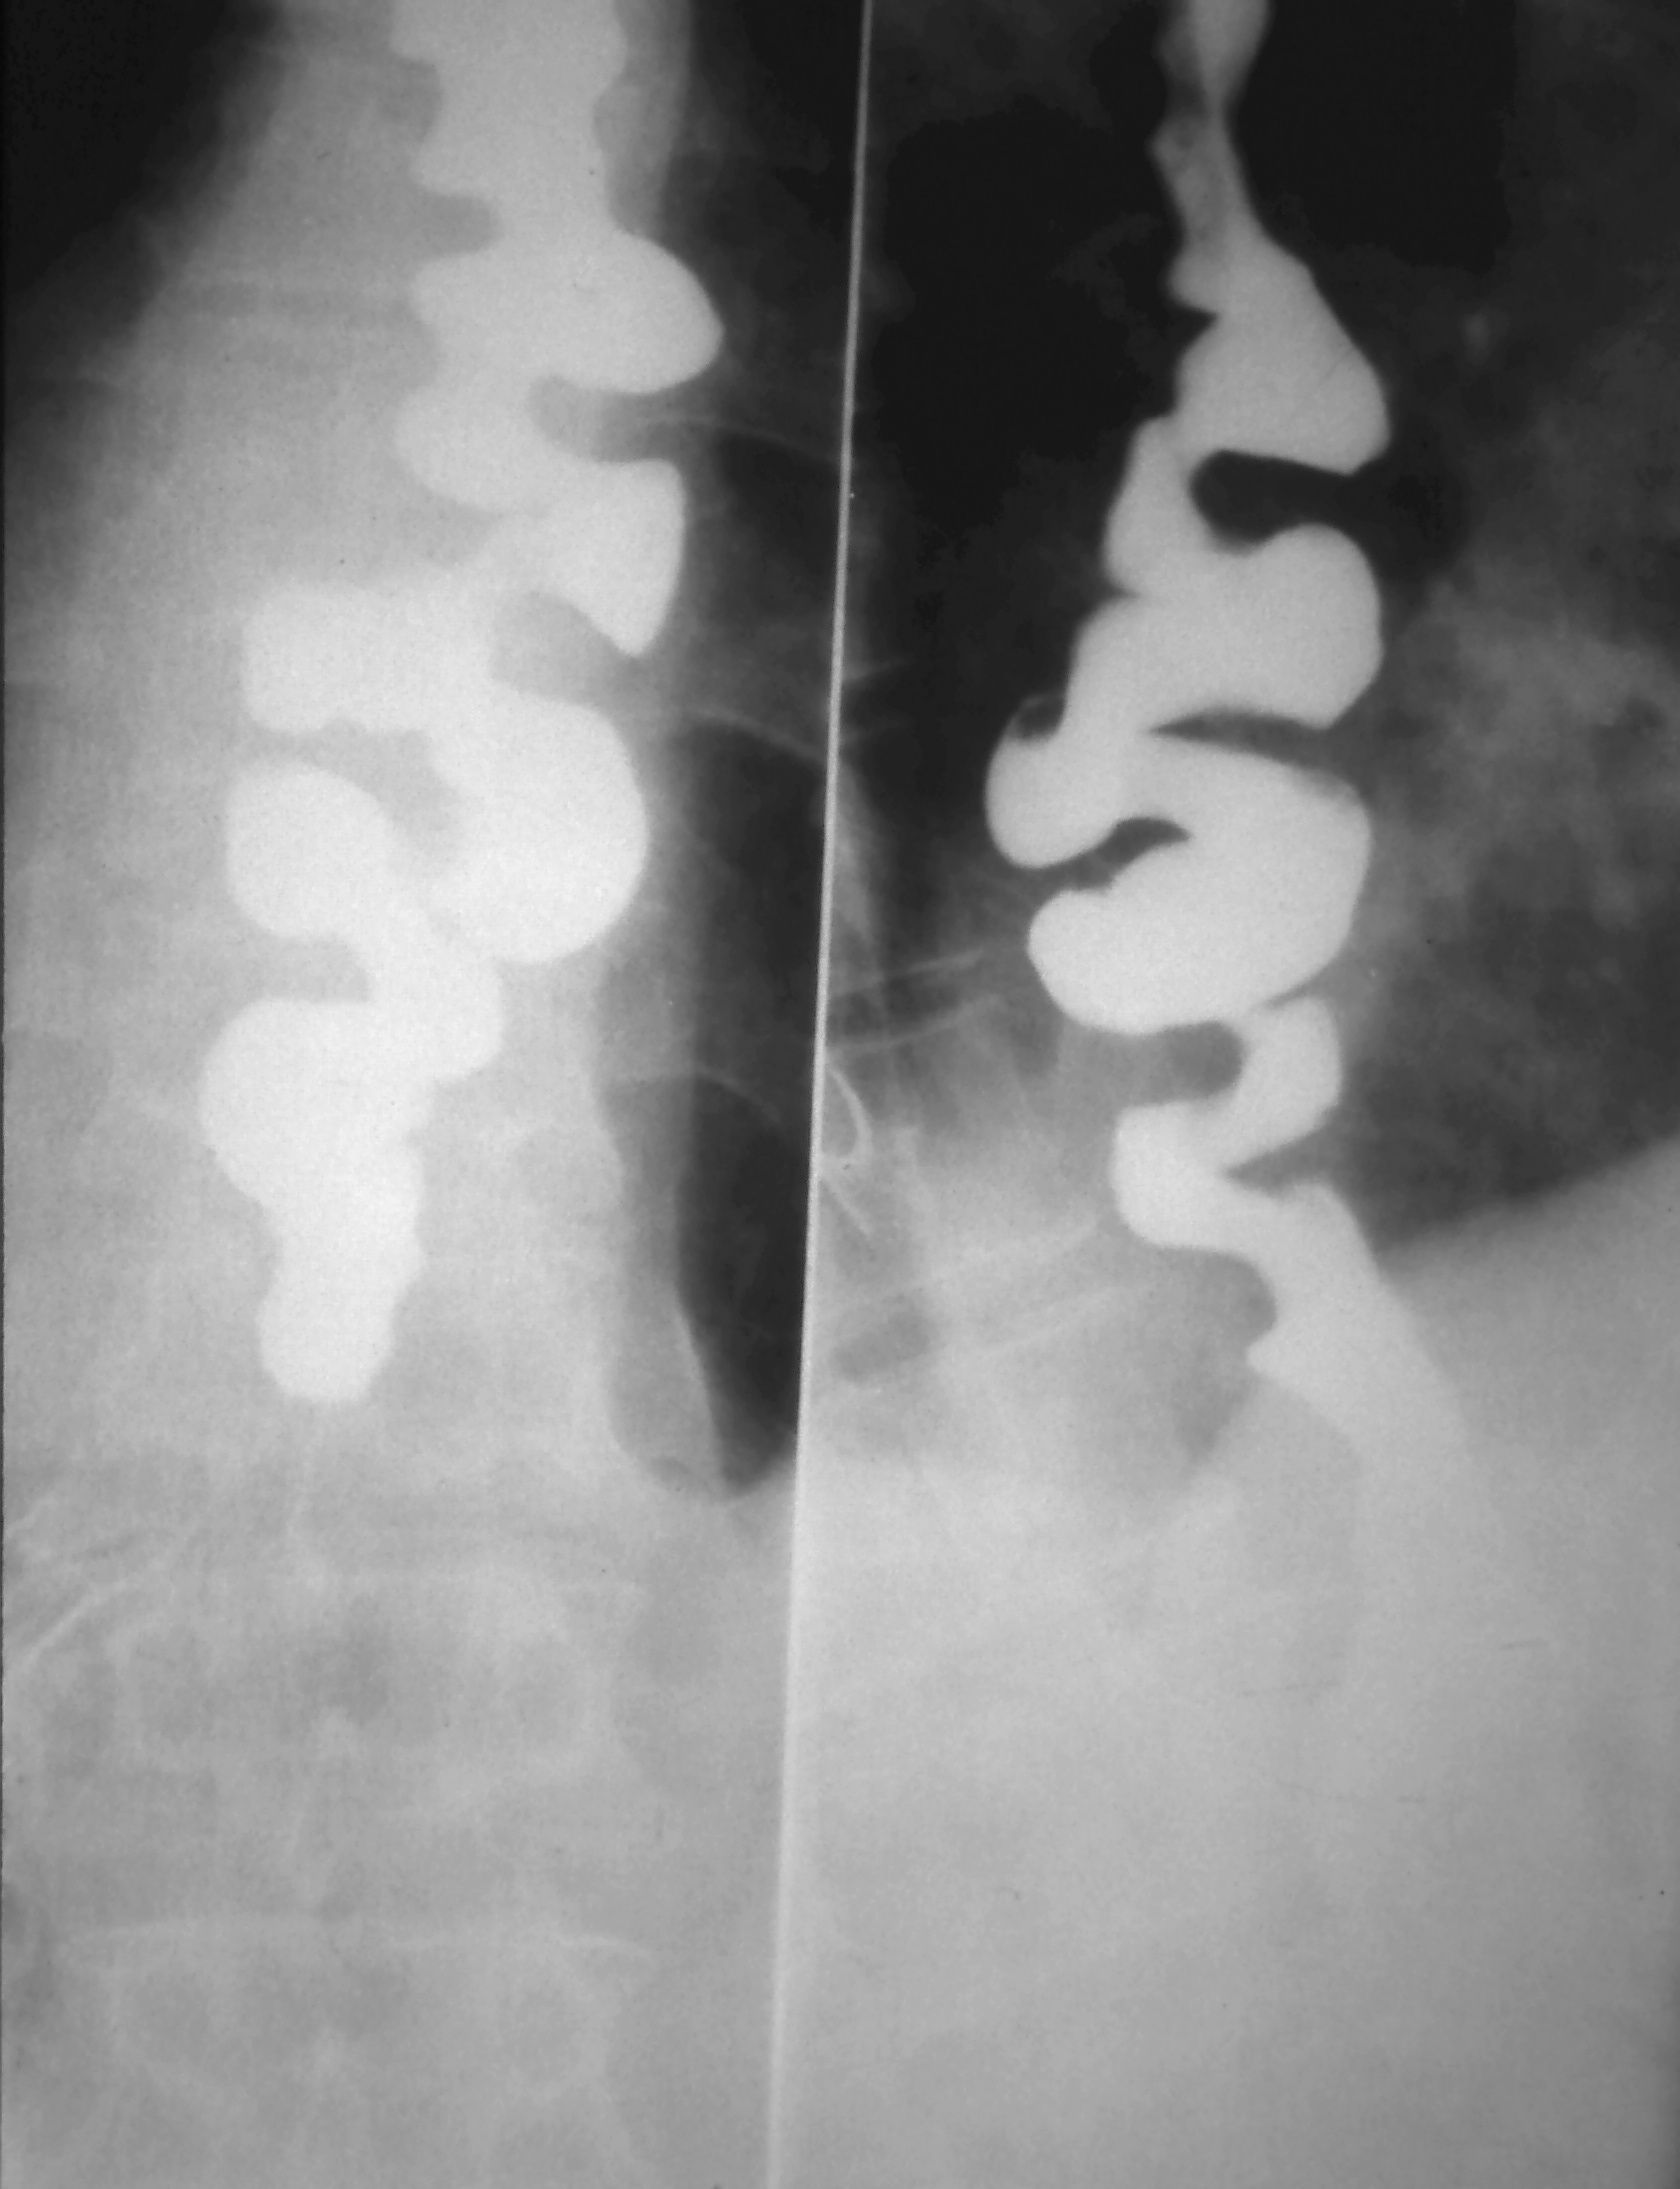

"Corkscrew appearance" on Barium Swallow in a patient with Diffuse Esophageal Spasm

Corkscrew Sign